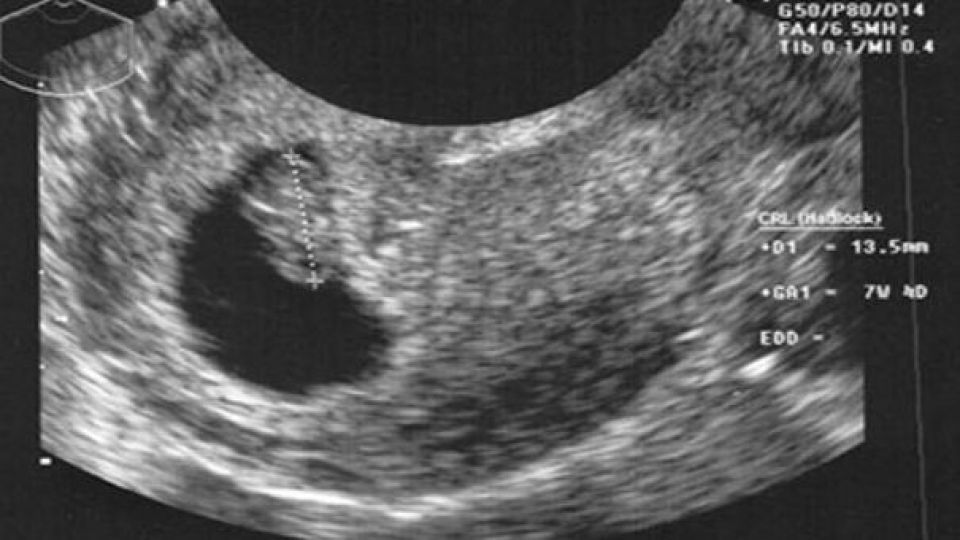

В ожидании чуда: цветное УЗИ и эмоции будущих родителей